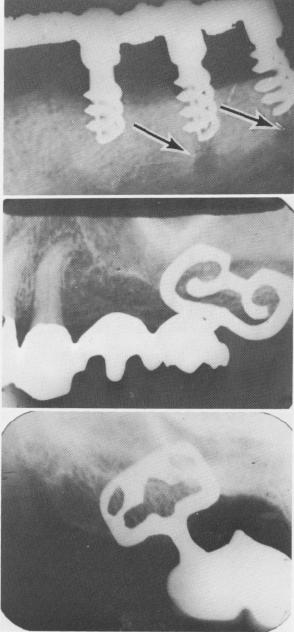

Fig. 14-15. A, Failure of implants resulted from the fact that the implants met too much resistance from the bone and therefore could not be screwed as deeply as the pre-ceding bone burs. As a result, the spirals were not buried deep enough under the fibromucosal tissue, which led to bone resorption. (From Linkow, L. I.: Alloplastic implants. In Goldman, H. M., Forrest, S. P., Byrd, D. L., and Mc-Donald, R. E.: Current therapy in dentistry, vol. 3, St. Louis, 1968, The C. V. Mosby Co., pp. 335-356.) B and C, Although sufficient bone existed, a portion of the shoulders of each one of the blade implants was not buried under the alveolar crest. Although these implants are still functioning satisfactorily in the mouth, this error could lead to failure.

1 Spiral shaft implants set through & below mandibular canal

2 Implants failed because of too much resistance from jaw bone